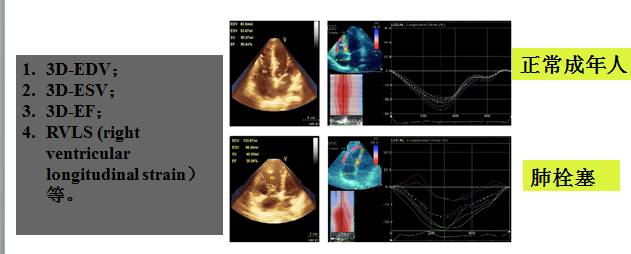

超声新指标—斑点追踪超声心动图

◆一些新技术如1D、2D应变以及3D超声也逐步应用于右心功能的评估